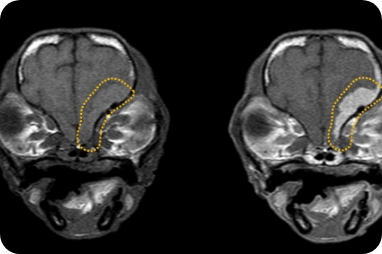

뇌두수증